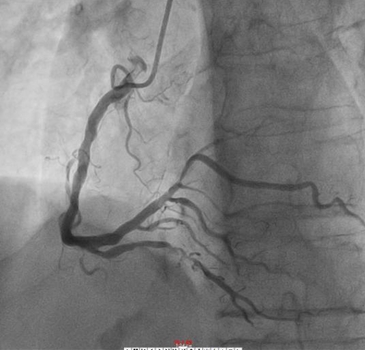

今年1月,患者梁伯因反复活动胸闷气短到我院住院治疗。梁伯是个老烟民,在入院后完善相关检验检查后,考虑诊断为不稳定型心绞痛。随后在进一步完善冠脉造影后,提示梁伯的右冠重度钙化,全程管腔不规则狭窄,其中远端狭窄达85%,需要尽快进行介入手术治疗。于2月23日进行手术后,造影显示冠状动脉右冠远端有明显狭窄伴钙化。经李龙虎主任医师手术团队讨论后,决定为梁伯采用Shockwave血管内冲击波钙化碎裂术,经过5个周期的冲击波治疗,精确碎裂冠状动脉内膜和中膜下钙化病灶,随后顺利植入支架。

▲ 使用IVL之前

手术过程:送Shockwave 2.5-12mm C2球囊至RCA远段病变处,压力充盈至4ATM,触发10个冲击波脉冲松解钙化斑块,然后充盈压升至6ATM维持10s对病变行低压球囊扩张成形,然后球囊泄压10s恢复靶血管而管灌注,此为1个治疗周期。重复上诉操作,总计2.5-12mm C2球囊输送5个治疗周期。